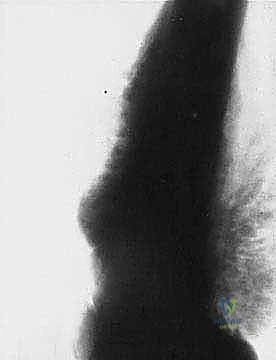

* الساركوما العظمية (Osteosarcoma): الأكثر شيوعاً، تظهر عادة حول الركبة (أسفل الفخذ أو أعلى القصبة).

المرحلة الأولى: استئصال الورم (Resection)

يتم فتح الجلد والأنسجة بعناية فائقة. التحدي الأكبر هنا هو فصل الورم عن الأوعية الدموية والأعصاب الرئيسية المغذية للطرف. يستخدم الدكتور هطيف تقنيات الجراحة الميكروسكوبية لضمان سلامة هذه الهياكل الحيوية، مما يحافظ على حيوية الطرف وحركته.